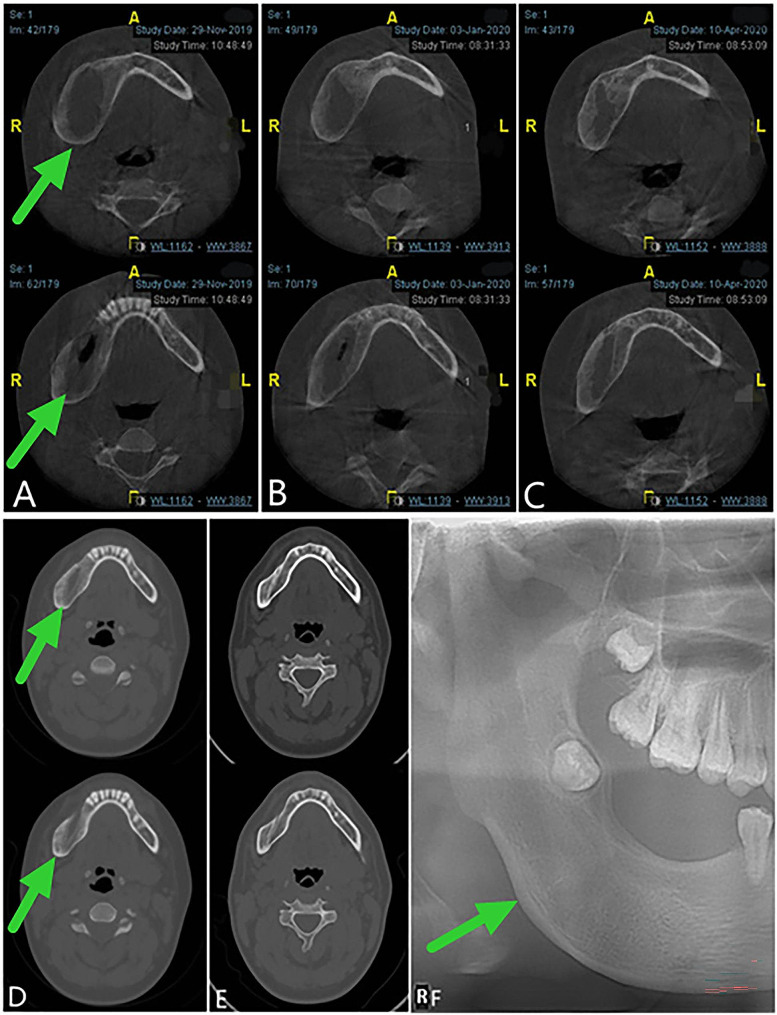

Fig. 5.

Follow-up images. A, B and C, Cone beam computed tomography showing 5, 7,10 months respectively after the second operation. D and E, Computed tomography view displaying the continuous osteogenic remodeling 4 and 15 months after the window is closed. F, Panoramic oral radiogram demonstrating 15 months after the surgery to close the window

After evaluation by our team, the child underwent stage II surgery in our hospital 4 months after the first operation (2019-08-01) to close the window, and the lesion was further clarified. During the operation, we found that the bone cavity in the opening window became shallow and narrow. The incision was made along the edge of the opening window, and the mucosa of the bony cavity and the surface part of the oral mucosa were excised together. The mucoperiosteal flaps on both sides were released, and the opening window was closed and sutured. The postoperative paraffin-embedded section indicated hyperplastic fibers and mucosal epithelium, and a small amount of reticular hyperplasia of the squamous epithelium was observed focally (Fig. 2D). Combined with the medical history, AM was not excluded. The child was followed up for 28 months after surgery (28 months after curettage and fenestration and 24 months after secondary curettage and fenestration closure). The operation area continued to have good osteogenic remodeling, and the bone appearance was improved without recurrence (Fig. 8).

Fig. 8.

Panoramic radiography and computed tomography. A, B and C, Panoramic oral radiogram showing 2 months, 1 year and 2 years respectively after secondary curettage and fenestration closure. D and E, Computed tomography view displaying 4 months and 28 months after the curettage and fenestration